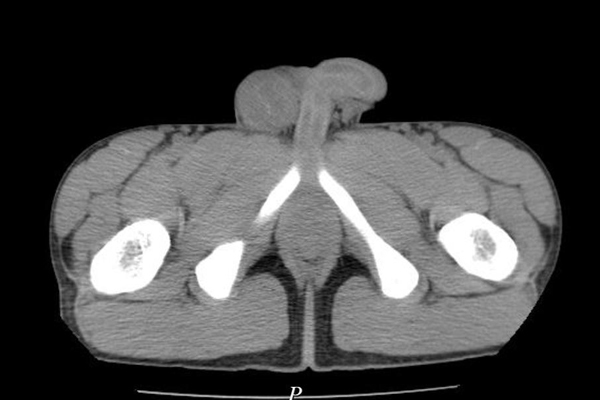

Hình ảnh các khối u đặc cứng trong bìu phải bệnh nhân

Qua kiểm tra và thăm khám, các bác sĩ nhận thấy bên vùng bìu phải có dấu hiệu sưng to, kích thước 7x8 cm, ấn đau và xuất hiện cục cứng chắc.